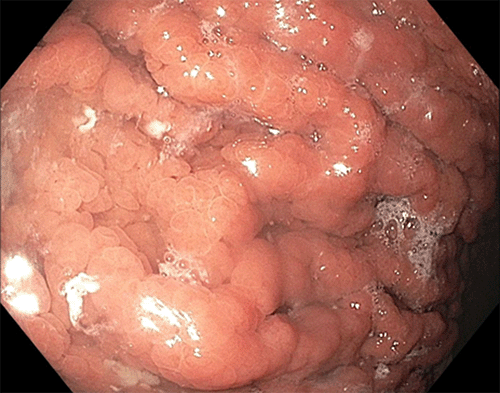

In the first case, the patient, a 37-year-old Caucasian male, presented with a one-year history of intermittent left upper quadrant abdominal pain. His past medical and surgical history was significant for obesity (BMI 39 kg/m2), hypertension, hyperlipidemia, Hashimoto’s thyroiditis, and inguinal hernia repair. He had a history of prolonged NSAID use but no history of smoking or significant alcohol consumption. His symptoms transiently improved with proton pump inhibitors (PPI) and antacids. He had a family history of gastric and colonic polyps in his father and bladder cancer in his paternal aunt. He had no family history of gastric cancer. Based on his symptoms, he was referred to gastroenterology. He underwent an esophagogastroduodenoscopy (EGD) that revealed multiple gastric polyps in the fundus and body of the stomach with antral sparing (Figure 1 and Figure 2), no polyps in the duodenum, and Los Angeles grade A reflux esophagitis. Biopsies were obtained and returned as fundic gland polyps without evidence of dysplasia on pathology. He underwent a colonoscopy that revealed small internal hemorrhoids and diverticula. No polyps were identified. His serum gastrin level was normal. The patient was referred for genetic counseling and testing and was found to have the c.-191T>C mutation in the APC promoter region seen in the setting of GAPPS. The patient had no known history of familial cancer syndrome. He had no evidence of metastatic disease on CT of the abdomen and pelvis.

Figure 1. Gastric Body—Extensive Polyposis With Heterogenous Polyps. Published with Permission